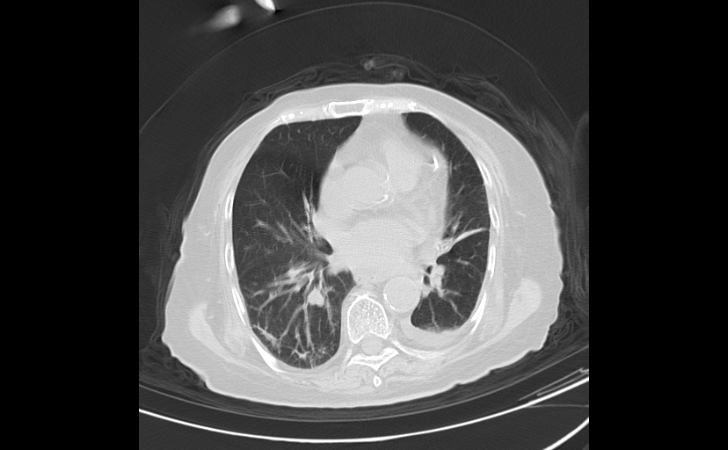

更严重的是,经过胸部CT检查,骆奶奶双肺呈现“白肺”,血氧饱和度降低至85%。这种高龄且有基础疾病的“白肺”老人,死亡率非常高!

经过医护人员的全力治疗和精心护理,骆奶奶病情逐步稳定并好转,胸闷气急症状逐渐消失,血氧饱和度提高到95%,复查胸部CT,“白肺”明显吸收好转。

治疗前/治疗后